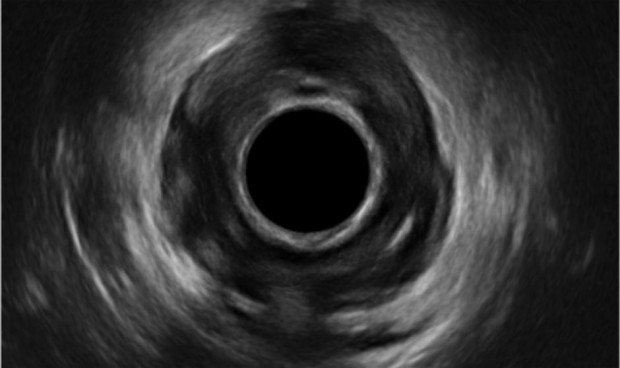

La Clínica HLA Montpellier incorpora a su área de Coloproctología una consulta de diagnóstico ecográfico de patología endoanal de última generación. La ecografía endoanal permite obtener imágenes mediante ultrasonidos del recto y del canal anal para valorar su anatomía y es uno de los mayores avances de la última década en la evaluación de la enfermedad anorrectal y del suelo de la pelvis.

Las indicaciones principales de la ecografía endoanal son el estudio morfológico del aparato esfinteriano en la incontinencia fecal, el estudio de localización de abscesos y fístulas perianales, la estadificación del cáncer de ano, así como el estudio evolutivo después del tratamiento conservador del cáncer epidermoide, y el estudio del aparato esfinteriano en pacientes con fisura de ano.

Esta prueba aporta información en casi todas las enfermedades del ano, como infecciones y supuraciones anales, tales como fístulas o abscesos anales: permite determinar su tamaño y localización y valorar el recorrido de la fístula para poder ofrecer un mejor tratamiento (habitualmente quirúrgico).

También para tumores anales, valorando la infiltración de los tejidos y su tamaño; para fisuras anales, valorando la integridad del aparato esfinteriano; y por último, la incontinencia anal, ya que valora la integridad de los músculos de la continencia y de la defecación, determinando si hay una causa estructural de la incontinencia.